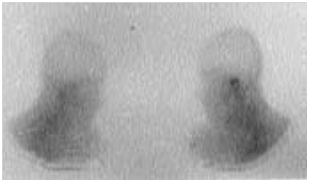

Figure 3 The left temporal bone shows an increased absorption of 67Ga (arrow).

The MEO is an otological infection that has life-threatening complications. It is considered as a complication of external otitis.2 Occurs mainly in the elderly who have diabetes or another condition that compromises the immune system. Doctors must be able to recognize this infection, initiate treatment, and refer patients to an Otolaryngologist. The precise etiology of this condition is unknown, but theories related to impaired immunity, the local tissue microangiopathie and even modified biochemistry of earwax have been proposed. Infection of the soft tissues of the external ear canal is common, especially in hot and humid climates. The usual triggers are trauma (often caused by q-tips) and exposure to the pool of water. The most frequently found germ is Pseudomonas aeruginosa, is not a normal germ of the EEC.3 Other possible germs include Staphylococcus epidermidis,4 gram negative bacteria and fungi. External otitis patients complain of earache and sensitivity to atrial movement. The otorrhoea may be present, the obliteration of the external ear canal by edema and secretions can cause hearing loss, or a feeling of fullness in the ear. The disease comes from the EEC and propagates through the osteo-cartilaginous junction to involve soft tissue under the temporal bone. Granulation tissue is usually present in the EEC. The spread of the infection can cause thrombosis of the lateral sinuses and petrous sinus upper and lower. Initially, the progressive skull base osteomyelitis can cause cranial Polyneuropathy, paralysis of the facial nerve being the most common; cranial nerves IX, X, and XI (the jugular foramen syndrome) nerves and cranial nerve XII (hypoglosse channel) are less often involved with the development of the sphenoidal sinusitis. Imaging to show the extension of the infection to the bony structures is usually required to establish the diagnosis of MEO6 imaging modalities include tomographic (CT) scan, scan bone to the technetium Tc99m medronate methylene diphosphonate, and scintigraphy to Ga 67 gallium citrate. CT is used to determine the location and extent of diseased tissue (Figure 1 & Figure 2). The temporal bone is the first os to be affected, with an imminent involvement of petrous apex and the mastoid process. Extratemporal extension has become rare since the introduction of powerful antibiotics. In evaluating the scanner, it is important to remember that at least one third of the minerals is lost before the radiological changes are becoming apparent; Conversely, the bone remineralization continued long after that infection is Gueriela scan is a diagnostic sensiblemais non-specific to the MEO, if to the 67Ga scintigraphy is available, (Figure 3). It must be used for the initial diagnosis and follow-up tool.7 Using in combination imaging modalities, it is possible to prove that the temporal bone is reached (scan and bone scan to the 99mTc) with infectious process (Ga 67 scintigraphy).6 MRI is of interest in advanced forms allowing a better analysis of the deep spaces of the face, the nervous foramina, merien hard spaces and the Medullary bone in the base of the skull.